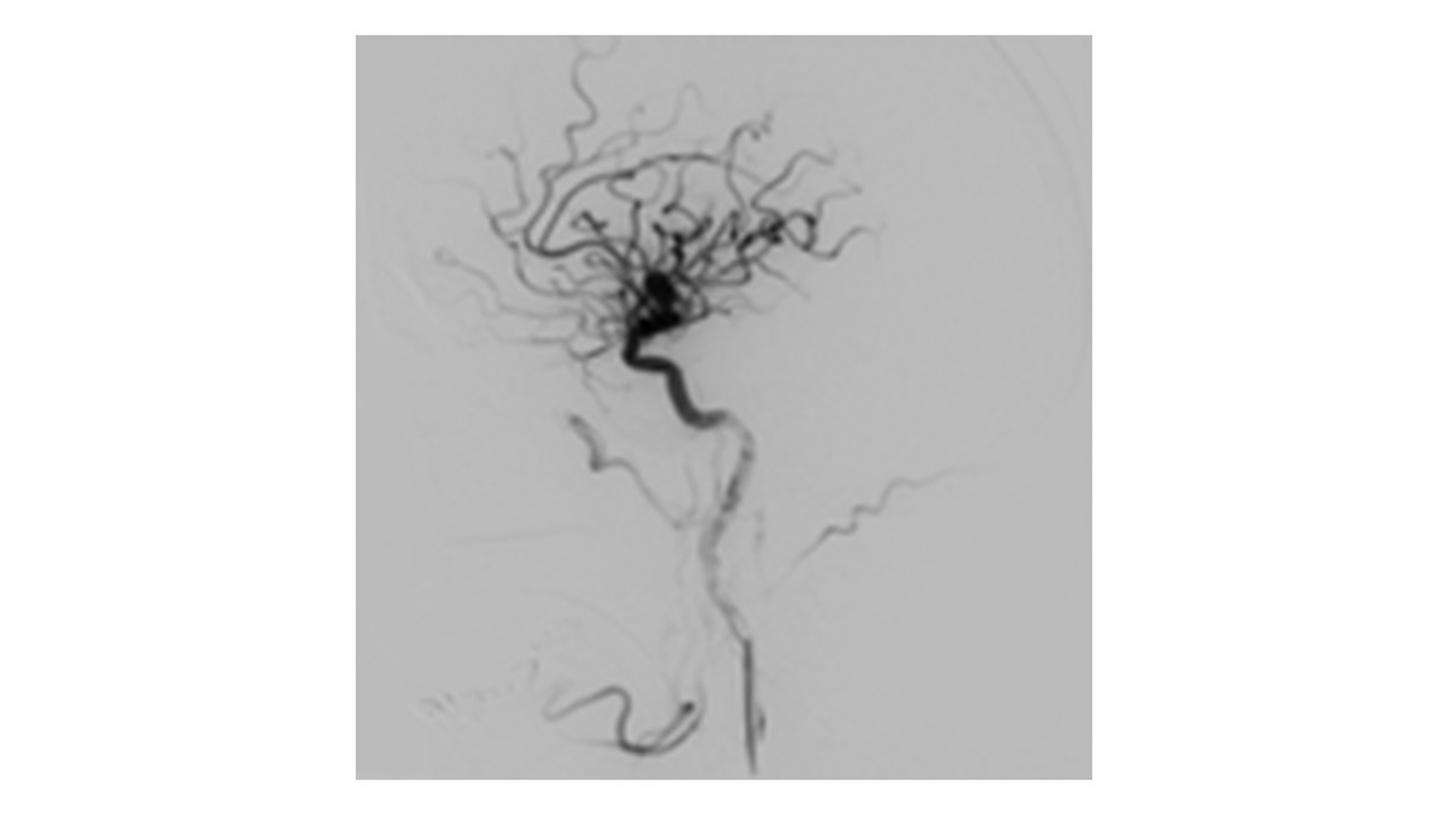

During minimally invasive procedures, it is critical to have a clear view of anatomies and devices. Yet complex imaging tasks or challenging patient conditions often impact image quality. OPTIQ AI delivers constant image quality1 defined by CNR in support of the ALARA principle, independent of patient or C-arm angulation. On top, an AI-powered algorithm reduces image noise in real time across different 2D imaging modes.

Make AI-powered imaging and clear insights your standard during interventions – with OPTIQ AI.